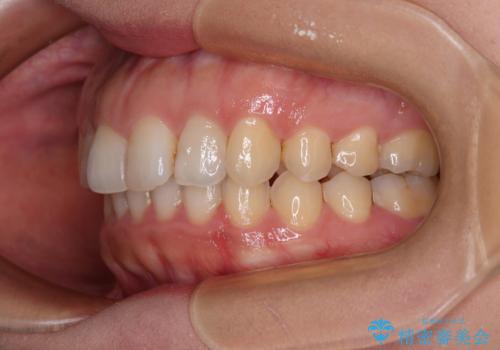

インビザライン矯正で前歯のデコボコを改善

- 前歯のデコボコを気にして来院された患者様です。

目立たないことを最優先にしたいとのことで、デコボコは軽度であったことから、インビザラインにて矯正治療を行うこととしました。

骨格的に下顎骨が左にずれており、上下の正中一致は困難ではありましたが、IPR(歯と歯の間を削る)や後方への移動など組み合わせて、できる限り改善しました。

インビザラインはマウスピースを外している時間が長いと、長期間使用しても前歯のデコボコはあまり改善されません。こちらの患者様は治療期間が長くなり、装着時間が短くなってしまったことで、気になる部分の改善により長期間を要するようになってしまいました。